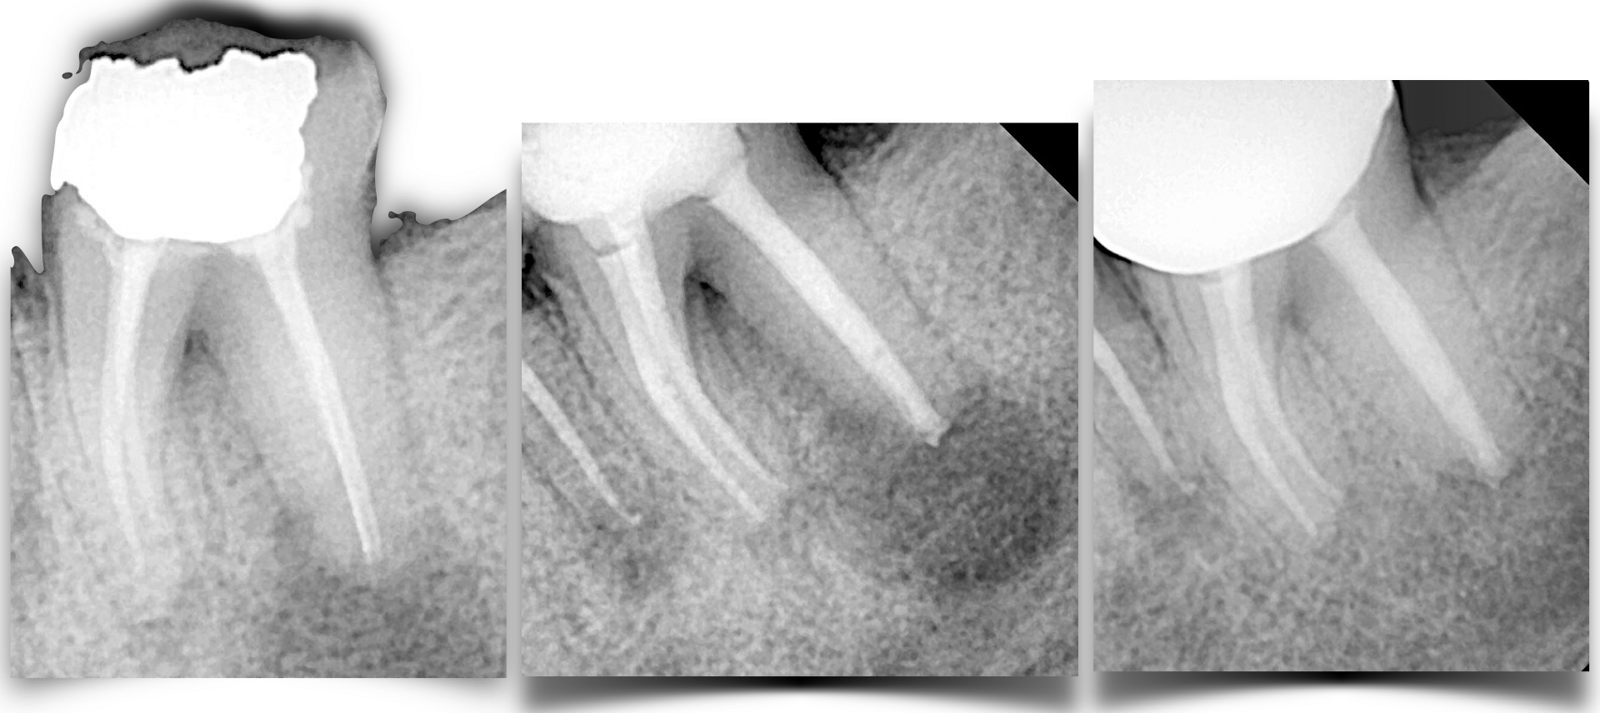

Figs. 1a–c: (a) Mandibular left second molar presented with unsuccessful primary treatment and symptomatic periapical periodontitis. (b) Non-surgical treatment involved an apical plug in the distal root. (c) One-year follow-up showed complete healing of the periradicular lesion.